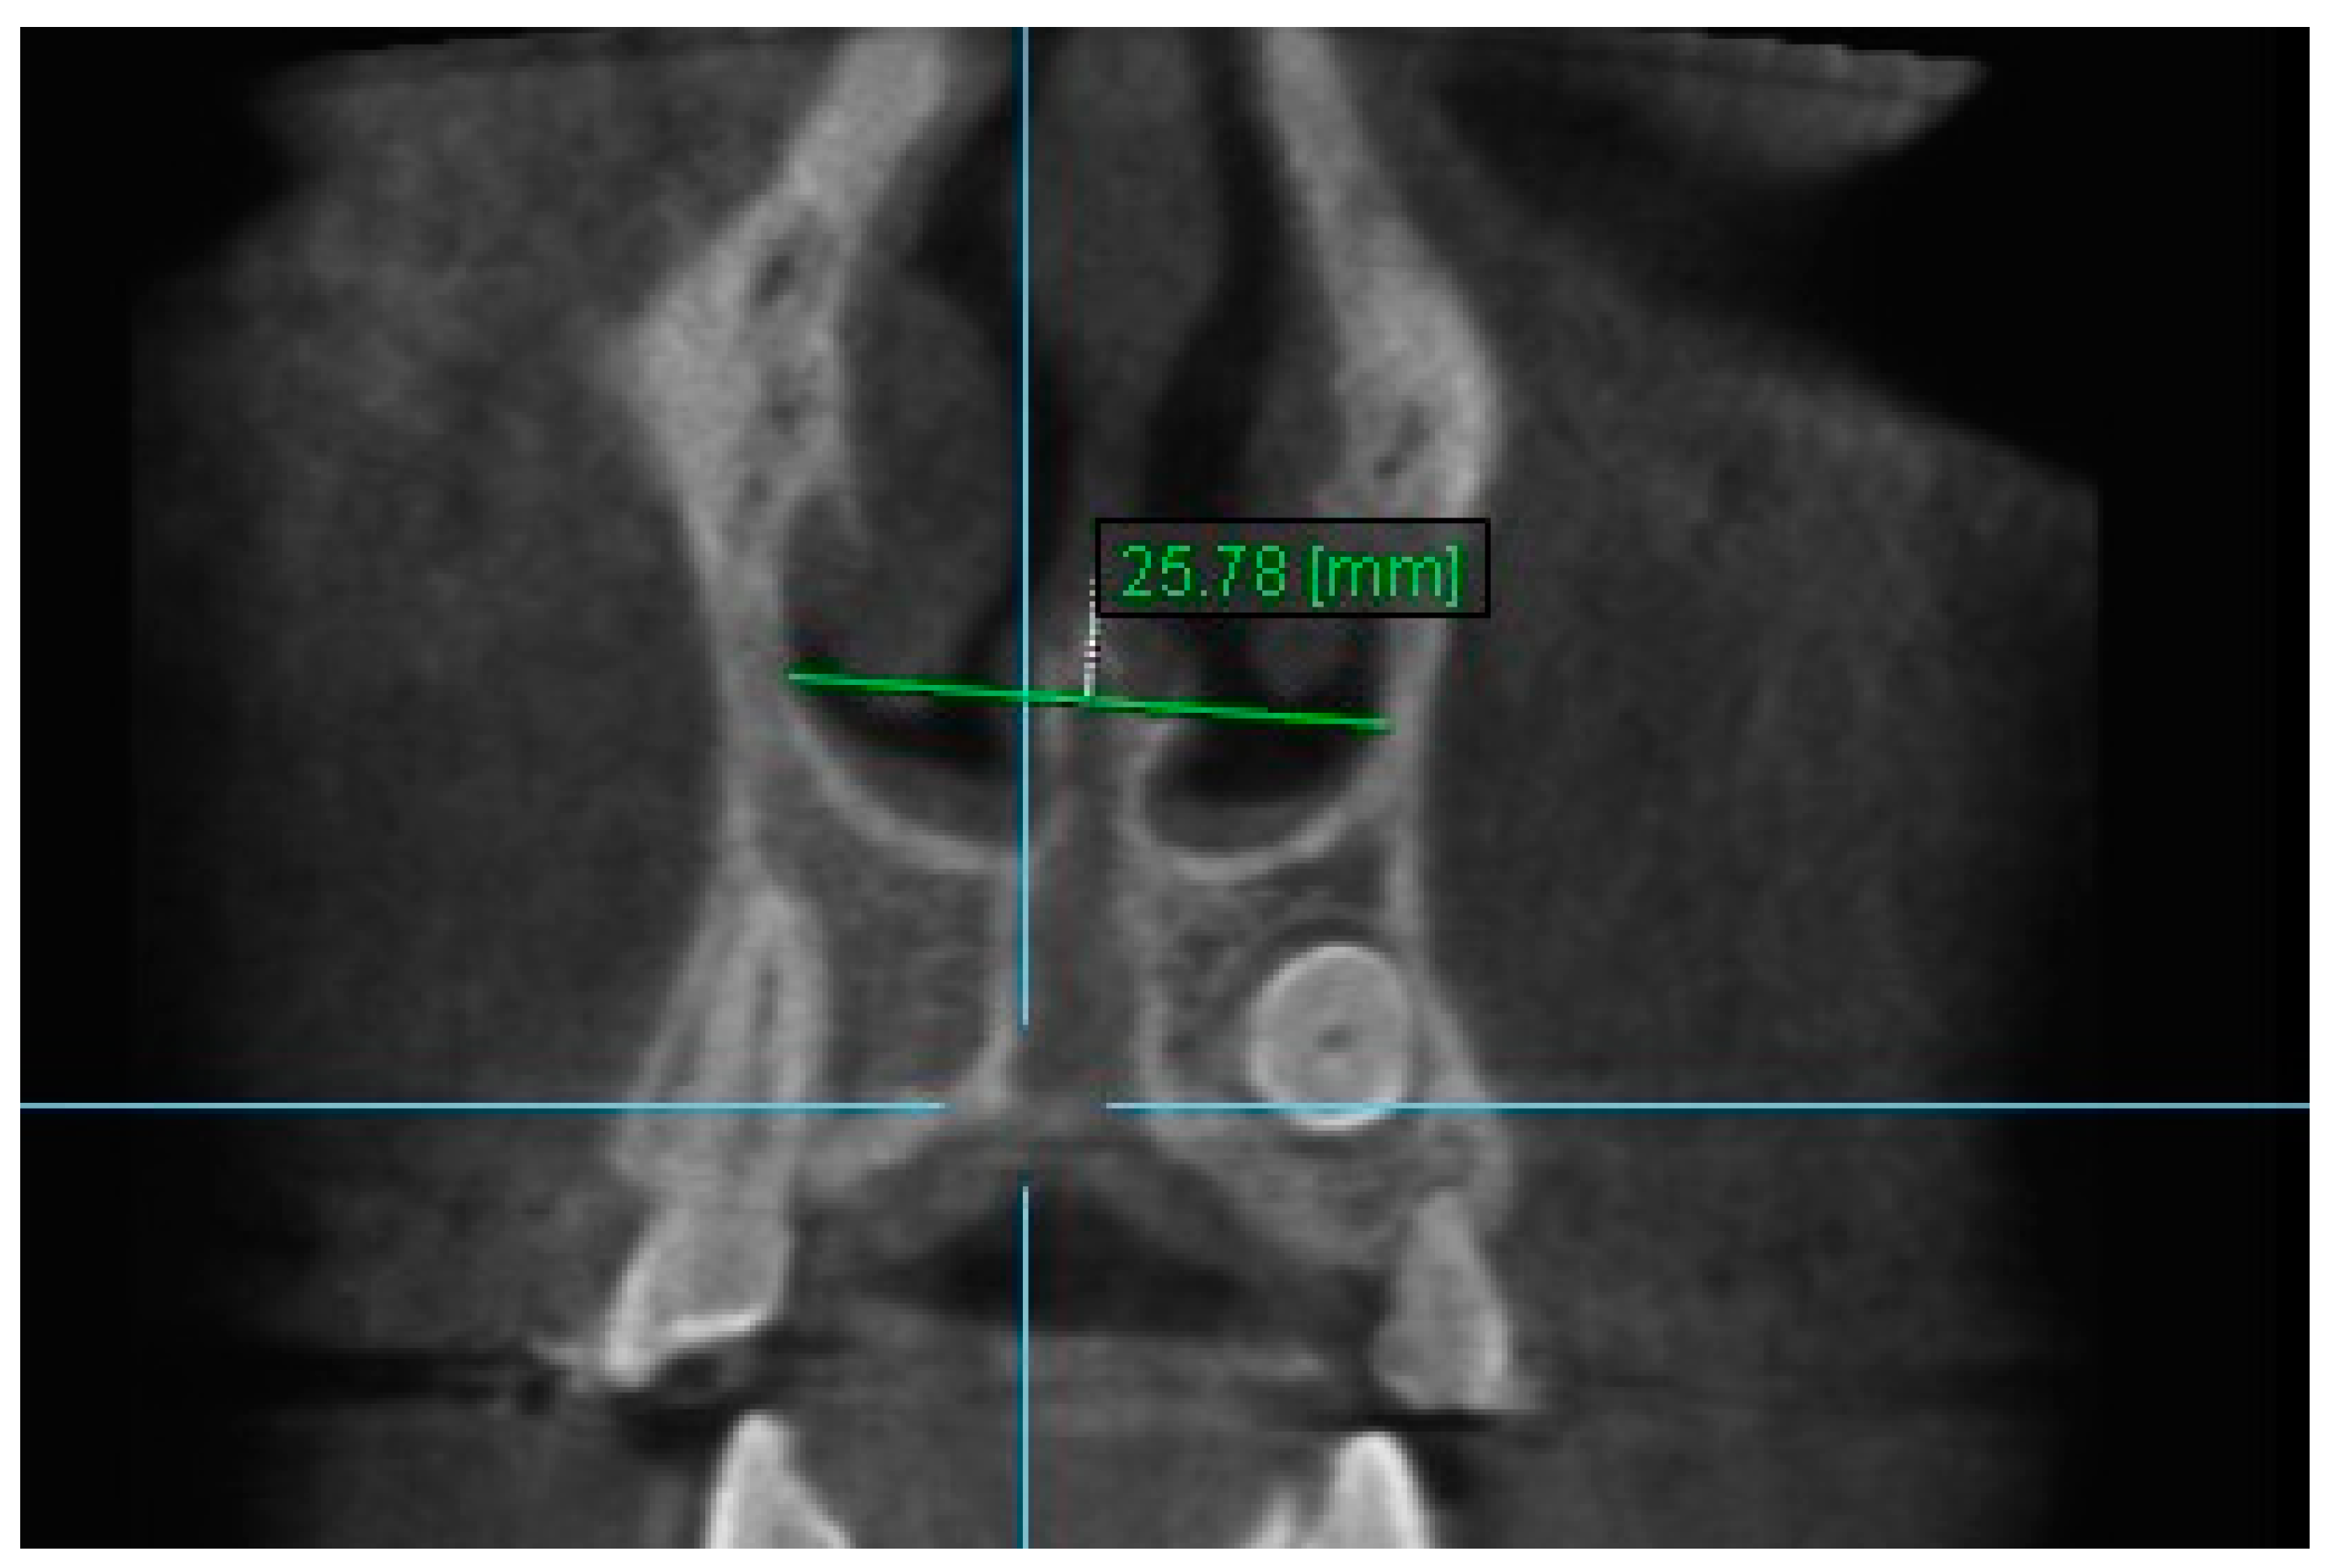

2. Nasal Width 2: The maximum lateral interior width of nasal cavity on coronal slice through the center of the root of the second premolar (Figure 4).

Figure 4.

Nasal Width 2.